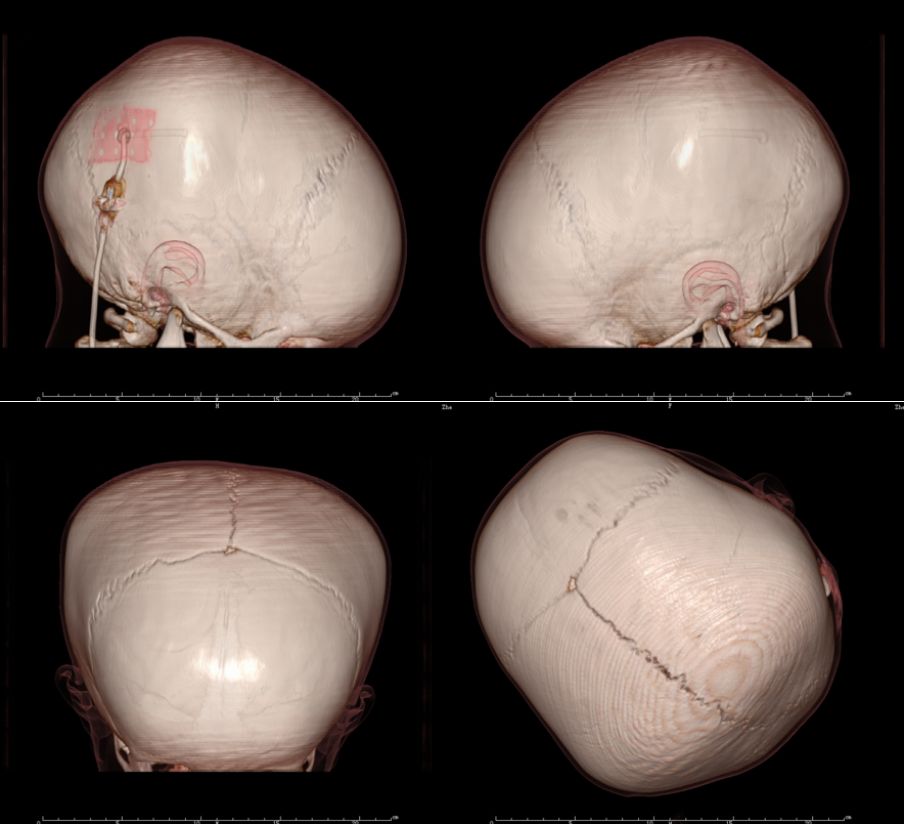

辅助检查:外院头颅CT示“重度脑积水”

入院后予完善相关术前检查,无明显禁忌后行脑室-腹腔分流术,当时植入为美敦立可调压分流管,术后压力为1.5。术后复查CT如图1。

图1. 脑积水分流术后复查CT:见侧脑室、三脑室增大明显,四脑室大小正常,考虑颅内出血后导致中脑导水管狭窄引起的梗阻性脑积水。